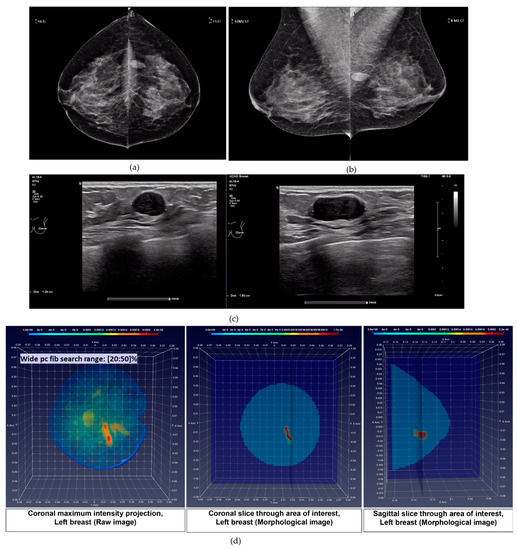

- Breast Lesion sizing: by means of fitting an ellipsoid to the ROI associated with the persistent lesion detection, in the 3D MBI images that have been generated by applying either of the two wide pc_fib search ranges. The greatest linear dimension of the lesion is defined as the length of the longest axis of the fitted ellipsoid. This definition is compatible with the conventional method that is applied for sizing breast abnormalities based on 2D mammography and ultrasound images [24,33]. During the FiH clinical investigation, the Wavelia MBI system showed promise for measuring lesion size with a more favorable linear trend between MBI and post-surgery histological lesion size, compared to the results obtained for conventional imaging [14]. Two challenging patient cases in terms of breast lesion sizing are indicatively discussed in Results Section 3.2, to better highlight the status of the MBI lesion sizing method, as integrated into the current version of the Wavelia QIF.

- pc_fib parameter setting in multiple search ranges: A large variability exists in the dielectric properties of each breast tissue type over the population, as demonstrated by multiple studies involving ex-vivo dielectric measurements of a large sample of excised breast tissues [18,19,20,21]. Considering that the full dielectric map of each breast cannot become practically available, data-driven techniques are employed in the Wavelia QIF to deduce the unknown dielectric properties of the healthy breast tissue in each breast, by assessing the pc_fib parameter. The pc_fib parameter, which is involved in the formulation of the illumination vector of the MBI sensor array, is physically associated with the percentage of fibro-glandular tissue along the propagation path within the breast, from a given transmitting antenna to the interrogated imaging pixel and back to a given receiving antenna, as defined in Equations (1)–(3). The Wavelia QIF generates a set of parametric MBI radar images under various assumptions on pc_fib. The generated set of parametric images is further evaluated in terms of focusing, using the image curvature [22,23] as a focusing quality measure. To better handle the heterogeneity of the breast and potentially better reveal the non-uniform angular response of the breast lesions to MBI, the pc_fib parameter setting is performed independently in each azimuthal imaging sector, while employing multiple search ranges. In the Wavelia QIF, X1 wide and X2 narrow pc_fib parameter search ranges are systematically employed for image formation, thus a total number of X = (X1 + X2) MBI images are formed per patient’s breast.

- Wide pc_fib search range #2 (W2): pc_fib ϵ [20 30 40 50]%